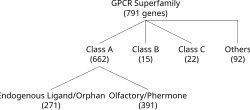

Bilateral frontoparietal polymicrogyria is a genetic disorder with autosomal recessive inheritance that causes a cortical malformation. Our brain has folds in the cortex to increase surface area called gyri and patients with polymicrogyria have an increase number of folds and smaller folds than usual.[1] Polymicrogyria is defined as a cerebral malformation of cortical development in which the normal gyral pattern of the surface of the brain is replaced by an excessive number of small, fused gyri separated by shallow sulci and abnormal cortical lamination. From ongoing research, mutation in GPR56, a member of the adhesion G protein-coupled receptor (GPCR) family, results in BFPP. These mutations are located in different regions of the protein without any evidence of a relationship between the position of the mutation and phenotypic severity.[2] It is also found that GPR56 plays a role in cortical pattering.[3]

The GPR56 is grouped in the B family of GPCRs. This GPCR group have long N termini characterized by an extracellular “cysteine box” and hydrophilic, potentially mucin-rich. The cysteine box contains four conserved cysteines and two tryptophans arranged in a specific fashion (C-x2-W-x6-16-W-x4-C-x10-22-C-x-C) just before the first transmembrane domain and serves as a cleavage site in some members of this group of G protein–coupled receptors.[7] Although, the molecular and cellular mechanisms of how GPR56 regulates brain development remain largely unknown.[8] These types of receptors play an essential role in biological processes including embryonic development, central nervous system (CNS), immune system, and tumorigenesis.[9]

Diagnostic criteria for a BFPP patient entails a heterozygous genotype for a deletion of chromosome 16q12.1-q21 region, including GPR56 gene.[10] To date the only gene known to be associated with polymicrogyria is GPR56. Testing for GPR56-related bilateral frontoparietal polymicrogyria is available clinically. Mutations in GPR56 hinders Collagen III, its specific ligand, to bind in a developing brain. To date, a total of fourteen BFPP-associated mutations have been identified, including one deletion, two splicing, and eleven missense mutations. Two mutations in the GPCR proteolytic site (GPS) domain, C346S and W349S, cause a brain malformation through trapping the mutated proteins in the endoplasmic reticulum.[11]

GPR56 are a part of the B class of the GPCR family, the largest cell surface gene family in the human genome. Within this family there are different types of bio-active molecules that transduce their signal to the intracellular compartment via interaction with this type of receptor. Children often present with developmental delay, spasticity, or seizures; they are also often microcephalic. Some patients with polymicrogyria go undiagnosed until they produce children with the disorder who have more severe manifestations. Retrospectively, these patients will often report some difficulty in their medical or educational history.[12] BFPP patients demonstrate mental retardation, language impairment, motor developmental delay, and seizure disorders such as epilepsy.[13] The association of epilepsy is in approximately 50% to 85% of affected BFPP patients.